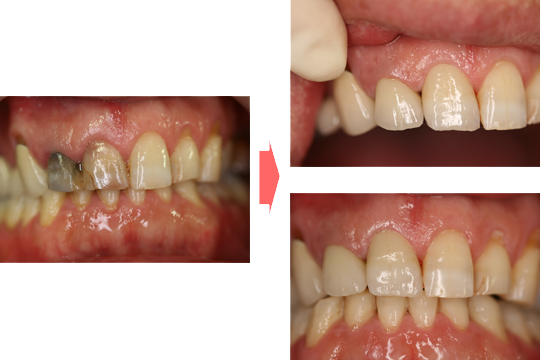

前歯部をオールセラミックによる審美的、機能的な回復をはかったケースです。

前歯ということで歯ぐきのラインにも気をつけより自然な仕上がりにしました。